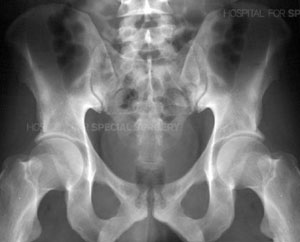

Radiograph of a normal pelvis

The complex nature of these fractures can be better understood by looking at the anatomy that is involved. The pelvis is made up of several bones (ileum, ischium and pubic bones) which create a bony ring, meeting at the pubic symphysis in the front and the sacrum (a bone situated at the lower end of the spine) in the back. Together with a number of ligaments and muscles, the bones of the pelvis support the weight of the upper body and rest on the hip joints. The pelvis protects abdominal organs including the intestines and the bladder, as well as major nerves and blood vessels. Pelvic fractures may occur at any location on the bones depending on the nature of the accident and the areas of impact.

Acetabulum refers to the part of the pelvis that meets the upper end of the thigh bone (the femoral head) to form the hip joint. In a healthy hip, these two bones fit together like a ball and cup, in which the ball rotates freely in the cup. Cartilage lines the bones where they meet at the joint and there is little friction between the surfaces during movement.